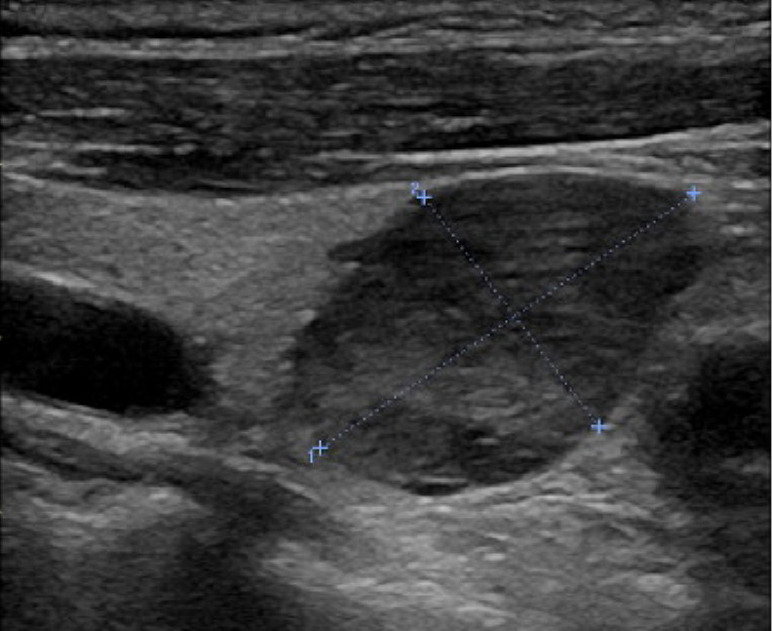

背景:甲状旁腺癌是一种罕见的内分泌恶性肿瘤。大多数病例为功能性甲状旁腺癌,而极少数为非功能性甲状旁腺癌。非功能性甲状旁腺癌患者的预后通常比功能性甲状旁腺癌患者差。这通常是由于非功能性甲状旁腺癌的隐匿性,通常导致较晚的发现和诊断。病例描述:2011年5月至2022年11月,浙江大学第一附属医院对6例诊断为甲状旁腺癌的患者进行了手术治疗。其中2名男性,4名女性,年龄从53岁到83岁不等。2例肿瘤位于右颈,4例肿瘤位于左颈。最小的肿瘤直径为2.5厘米,而最大的肿瘤直径为11.4厘米。2例为异常罕见的非功能性甲状旁腺癌,4例为功能性甲状旁腺癌。所有6名患者都接受了手术。病理类型包括主细胞型2例,混合细胞型2例,嗜氧细胞型1例,透明细胞型1例。随访时间为1 ~ 151个月。5名患者存活,1名患者死亡。无功能甲状旁腺癌患者均有复发和转移,Ki-67水平分别为30%和20%。相比之下,4例功能性甲状旁腺癌患者均无复发,1例Ki-67水平为20%,3例Ki-67水平为5%。结论:非功能性甲状旁腺癌患者预后不良可能反映了其生物学行为和较高的恶性潜能。Ki-67水平与甲状旁腺癌的恶性潜能呈正相关。这些推测仍然需要通过大规模的临床研究来验证。

Case description: Between May 2011 and November 2022, the First Affiliated Hospital of Zhejiang University conducted surgical treatment on six patients diagnosed with parathyroid carcinoma. Of these, two were male and four were female, with ages spanning from 53 to 83 years. The tumors were situated on the right neck in two cases and on the left neck in four cases. The smallest tumor measured 2.5 cm in diameter, whereas the largest measured 11.4 cm. Two cases were exceptionally rare nonfunctional parathyroid carcinomas, and four were functional parathyroid carcinomas. All six patients underwent surgery. Pathological types comprised the chief-cell type in two cases, the mixed-cell type in two cases, the oxyphil-cell type in one case, and the clear-cell type in one case. The follow-up duration ranged from 1 to 151 months. Five patients remained alive, while one patient died. Both patients with nonfunctional parathyroid carcinoma experienced recurrence and metastasis, with Ki-67 levels of 30% and 20%, respectively. In contrast, none of the four patients with functional parathyroid carcinoma recurred, with one case having a Ki-67 level of 20% and three cases with a Ki-67 level of 5%.